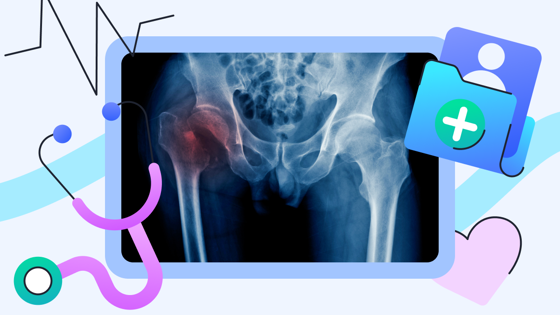

48 часов на операцию: как спасти родственника с переломом шейки бедра